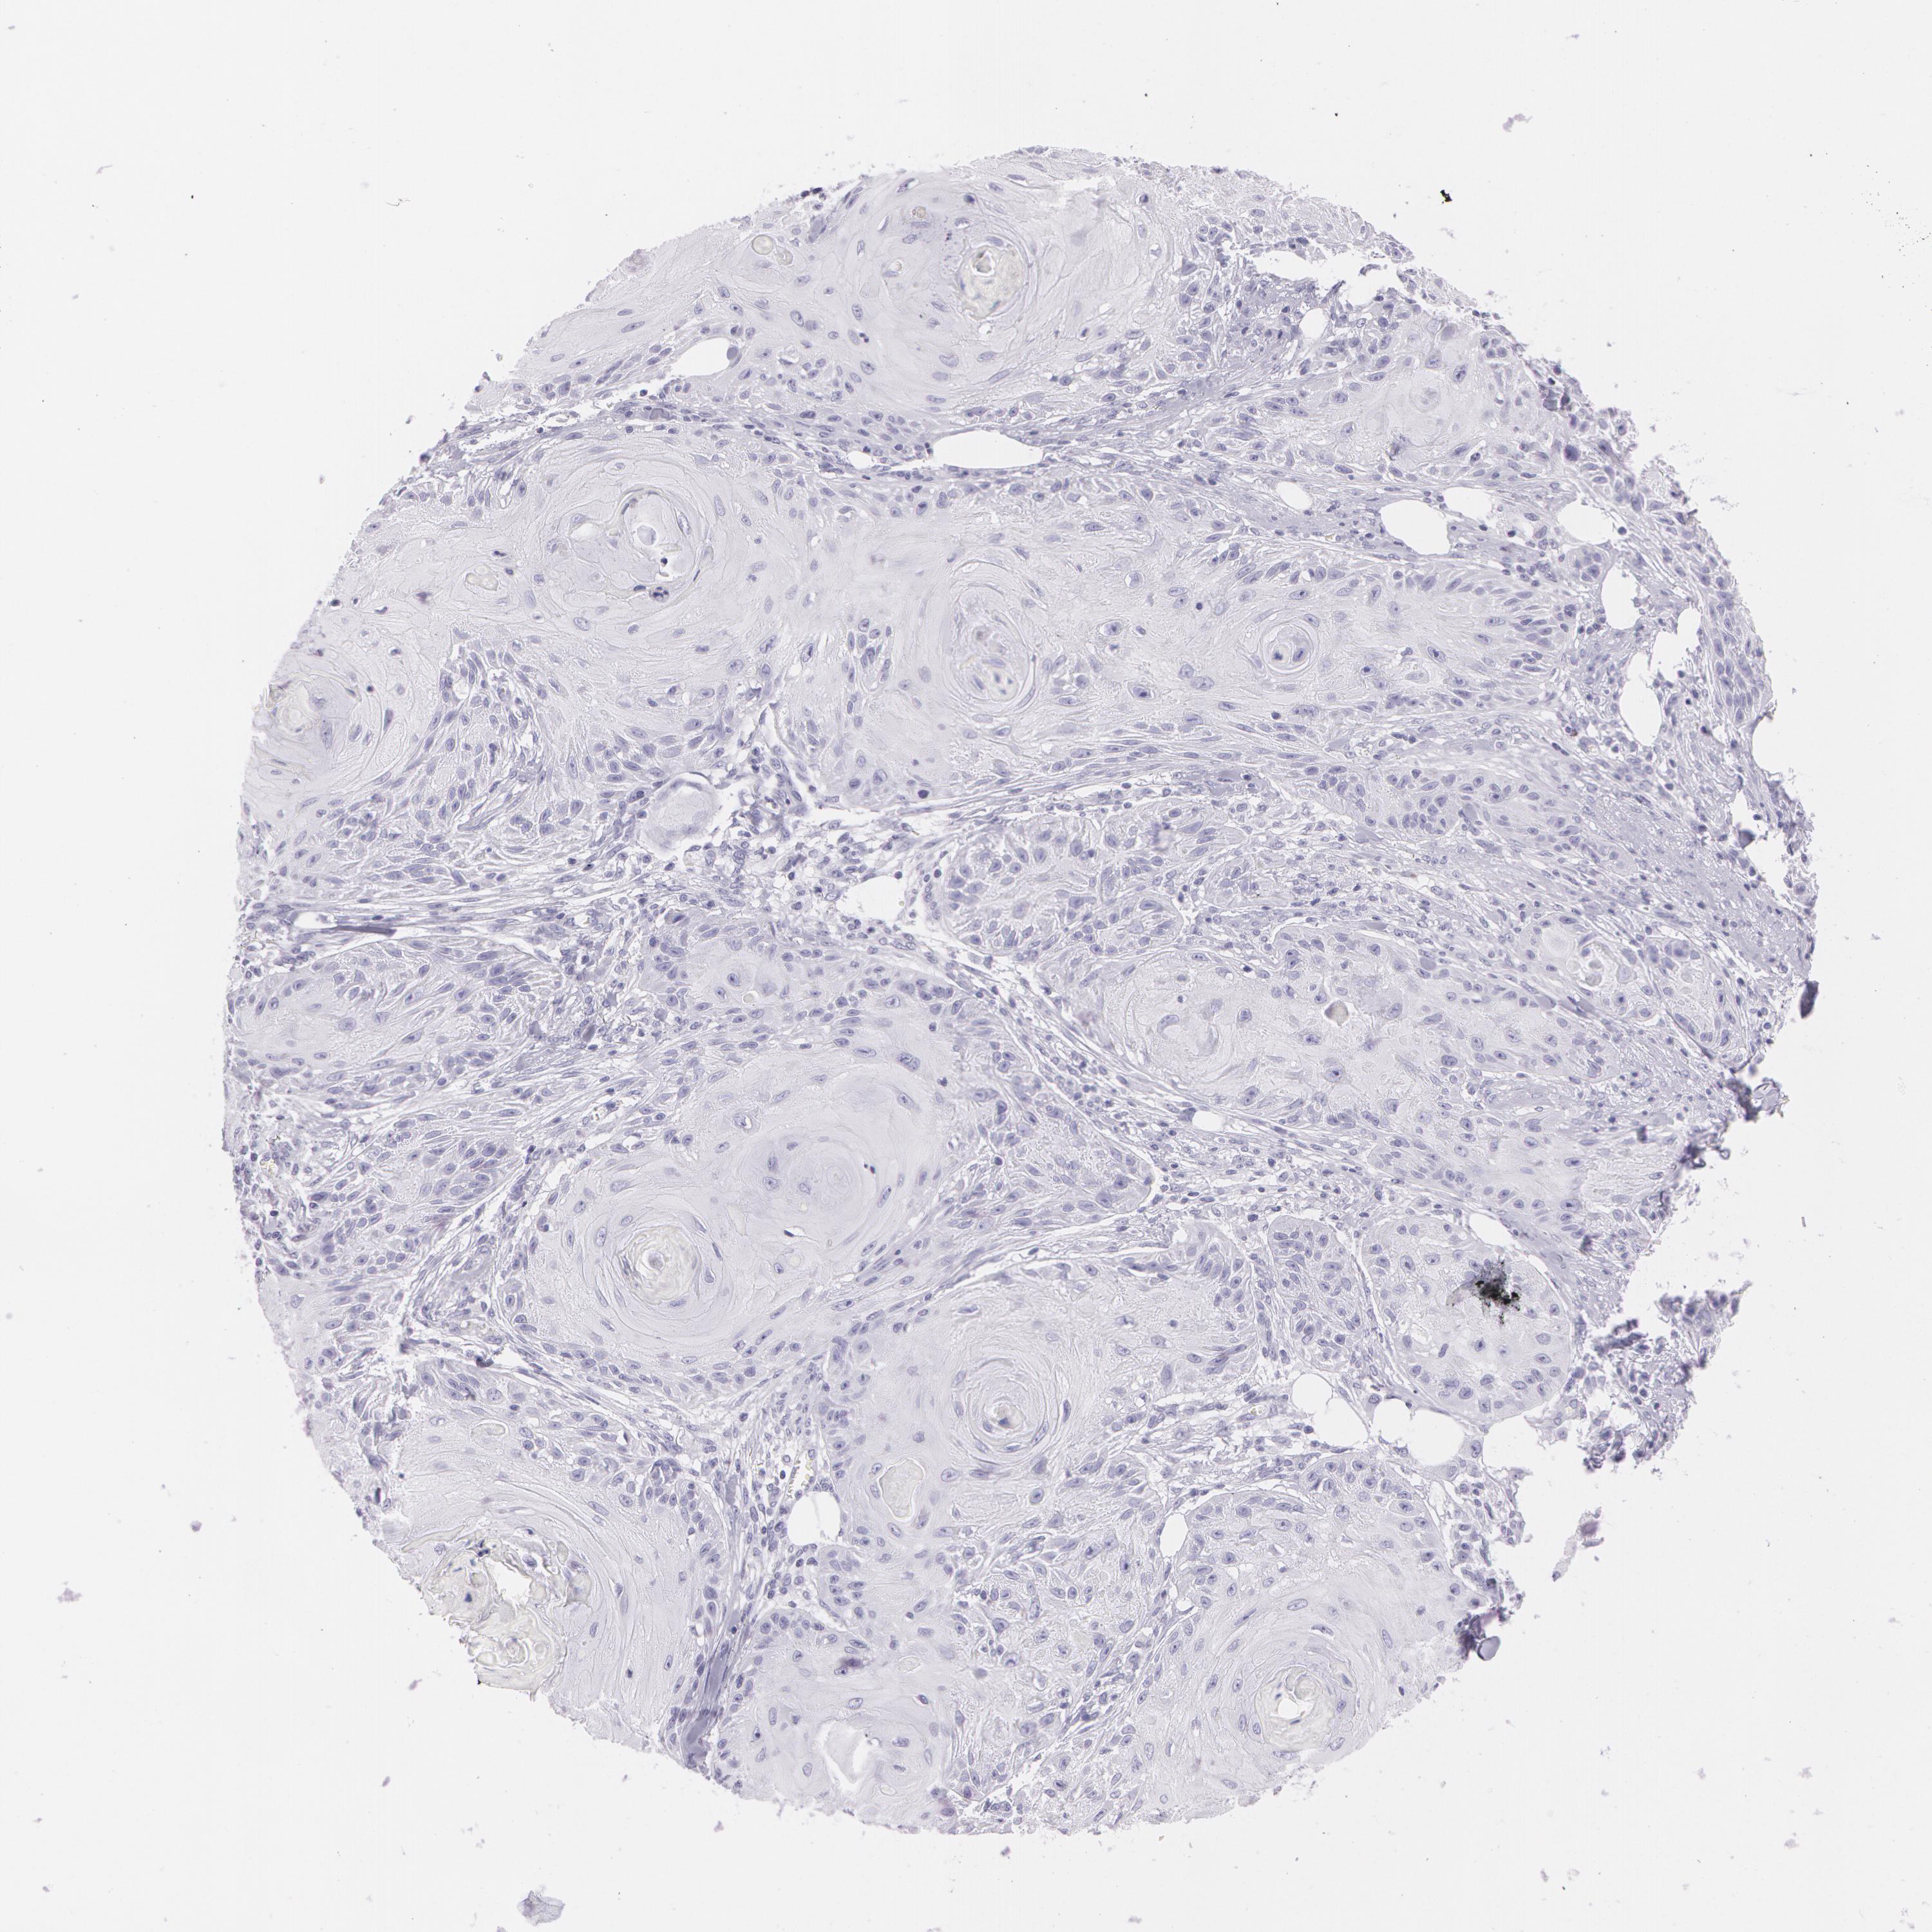

SKIN CANCER - Protein expressioni

A mouse-over function shows sample information and annotation data. Click on an image to view it in a full screen mode. Samples can be filtered based on level of antibody staining by selecting one or several of the following categories: high, medium, low and not detected. The assay and annotation is described here.

Each image is clickable and will lead to virtual microscopy that enables deeper exploration of all samples and also displays staining intensity scores, fraction scores and subcellular localization as well as patient and tissue information for each sample.

Antibody HPA014404

Squamous cell carcinoma, NOS